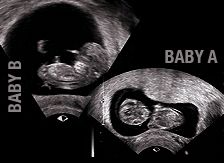

*IT SHOULD BE NOTED THAT THE PHOTO TO THE LEFT AND BELOWSHOWS BABY "B" IS READY TO BEGIN HIS BASEBALL CAP, DAWNING A BASEBALL CAP IN THE WHOMP (AND KNOW IS FATHER DID NOT COMPUTER ALTER THIS PHOTO IN ANY WAY.